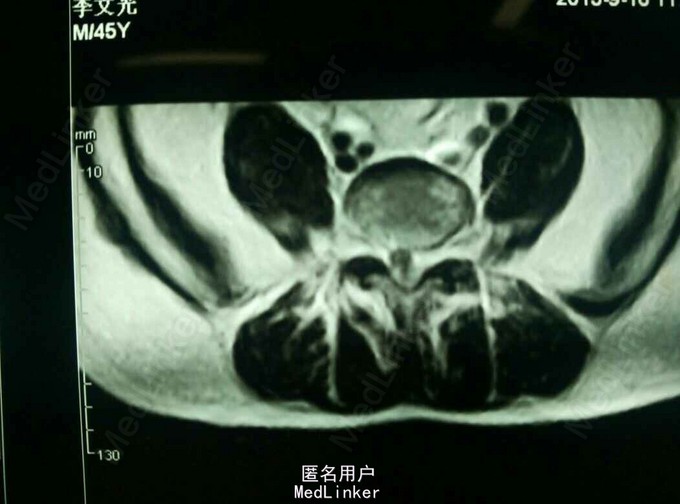

查体:脊柱无畸形,腰部L5S1间隙处轻压痛,脊柱无叩击痛,右小腿外侧及足底触痛觉减退,右下肢肌力4级,右下肢直腿抬高试验40度。 MRI提示:L5S1椎间盘脱出,髓核游离要椎管。

诊断:L5/S1椎间盘脱出(右侧) 治疗:因保守治疗效果不佳,准备行手术治疗。

请大家谈谈该患者的手术方案:开放融合内固定术?椎间盘镜手术?椎间孔镜手术?还是其他方案?